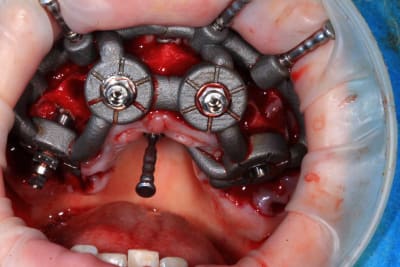

Guide métal avec support clavette, os assez fin : il est prévu un sticky bone complet : donc : lambeau avant extraction, positionnement du guide base et forage des clavettes, positionnement du guide implant, pose des piliers MU, controle des axes prothétique avec le guide pilier, collage des piliers prov sur le bridge a armature métal, occlusion nickel, sticky bone et PRF, sutures suspendues.

T’as quand même une sacrée déviation des implants / à la planification…..

Ça se voit déjà avec les implants posés à travers le guide de forage métallique qui est amha trop permissif

Et c’est confirmé par ton guide pour les piliers multiunits qui n’est même pas à fond (clavette antérieur pas mise….enfin certainement impossible à mettre)

Mais tu as raison, il y avait un peu trop de jeu au niveau du guide .

C’est le premier entièrement métallique que je fais imprimer ( Fridentech ). Il faut que je fasse un modèle avec plusieurs diamètres pour avoir le meilleur ajustage . Je pense que le mieux serait d’insérer une douille ETK. C’est ce que fait Dimitri avec ses guides métalliques codiagnostic.

Pour le guide pilier , c’était pile, mais je n’avais pas fais la photo. Je l’ai remis vite fais ( et mal ) pour la photo.

Le guide pilier est la réplique du bridge prov , en plus light pour une meilleure visibilité, donc, si je n’avais pas pu bien mettre le guide pilier, cela aurait été pire avec le bridge prov.

Mais tu peux me faire confiance.Le bridge prov était nickel, avec la clavette en place, sans que je ne doive meuler les puits préparés.